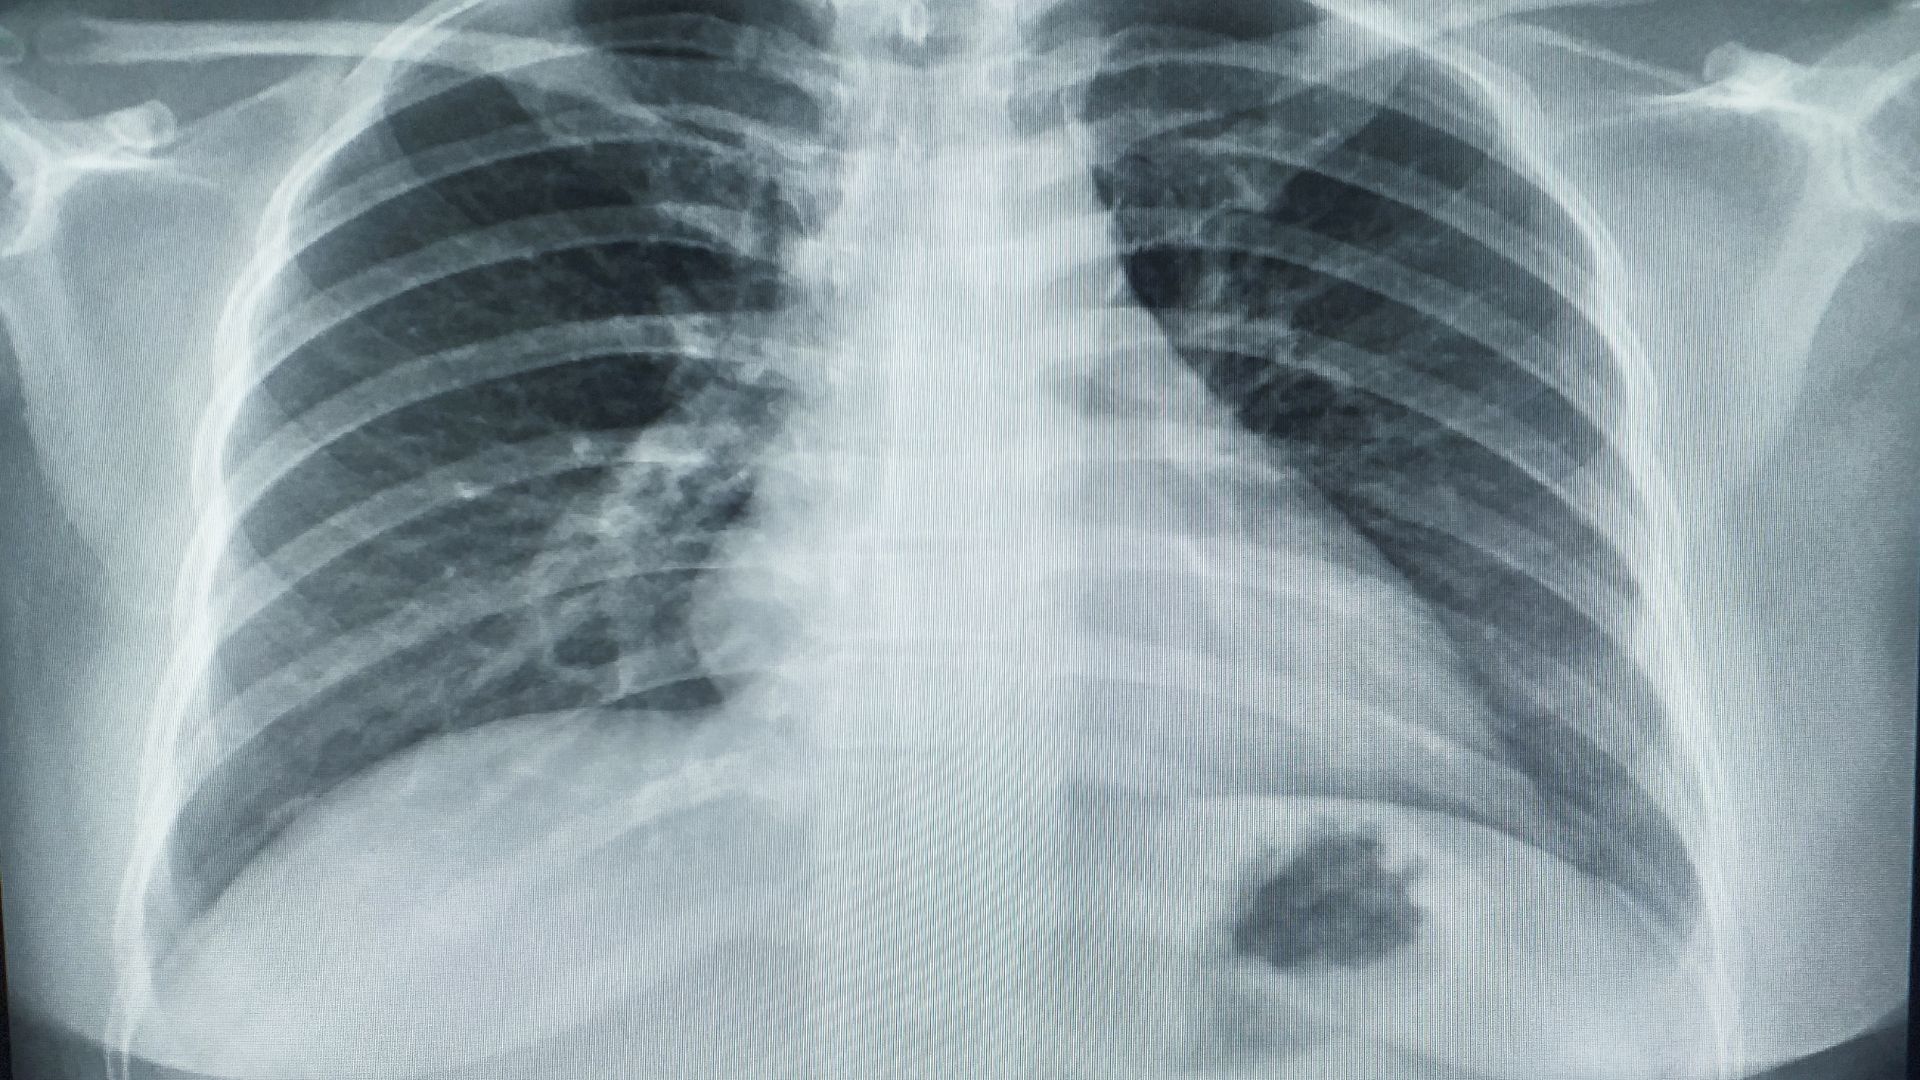

- Chụp X-quang phổi: X-quang là bước đầu tiên giúp quan sát tổng quát hình ảnh phổi. Hình ảnh có thể cho thấy các nốt mờ hoặc vùng bất thường. Mặc dù không thể đánh giá chi tiết nhưng đây là bước quan trọng để định hướng phương pháp tiếp theo.

- Chụp CT ngực: CT cung cấp hình ảnh rõ nét hơn giúp xác định chính xác kích thước và vị trí tổn thương. Nhờ khả năng cắt lớp CT hỗ trợ phát hiện những khối u rất nhỏ mà X-quang khó quan sát. Điều này đặc biệt quan trọng trong giai đoạn sớm của di căn.